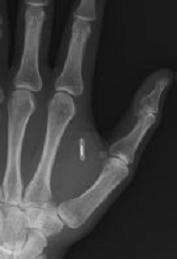

mano chippata Che i timori californiani possano essere fondati, peraltro, lo dimostra il favore con cui altrove il Verichip e l’impianto siano stati accolti. È noto, ad esempio, il caso dell’allora procuratore generale messicano Rafael Macedo de la Concha che nel 2004 non solo riempì le cronache del suo braccio con RFID incorporato, ma impose ai dipendenti del suo ufficio di farselo impiantare, pena l’impossibilità di accedere al proprio posto di lavoro.

Qui sotto un video danese che riprende l’impianto di un chip RFID nella mano: